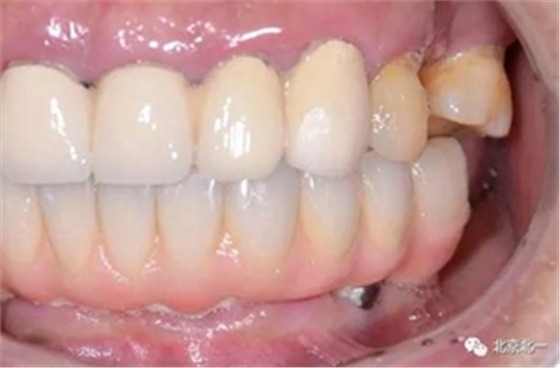

圖二十:永久修復(fù)咬合關(guān)系

圖二十五:口內(nèi)照。